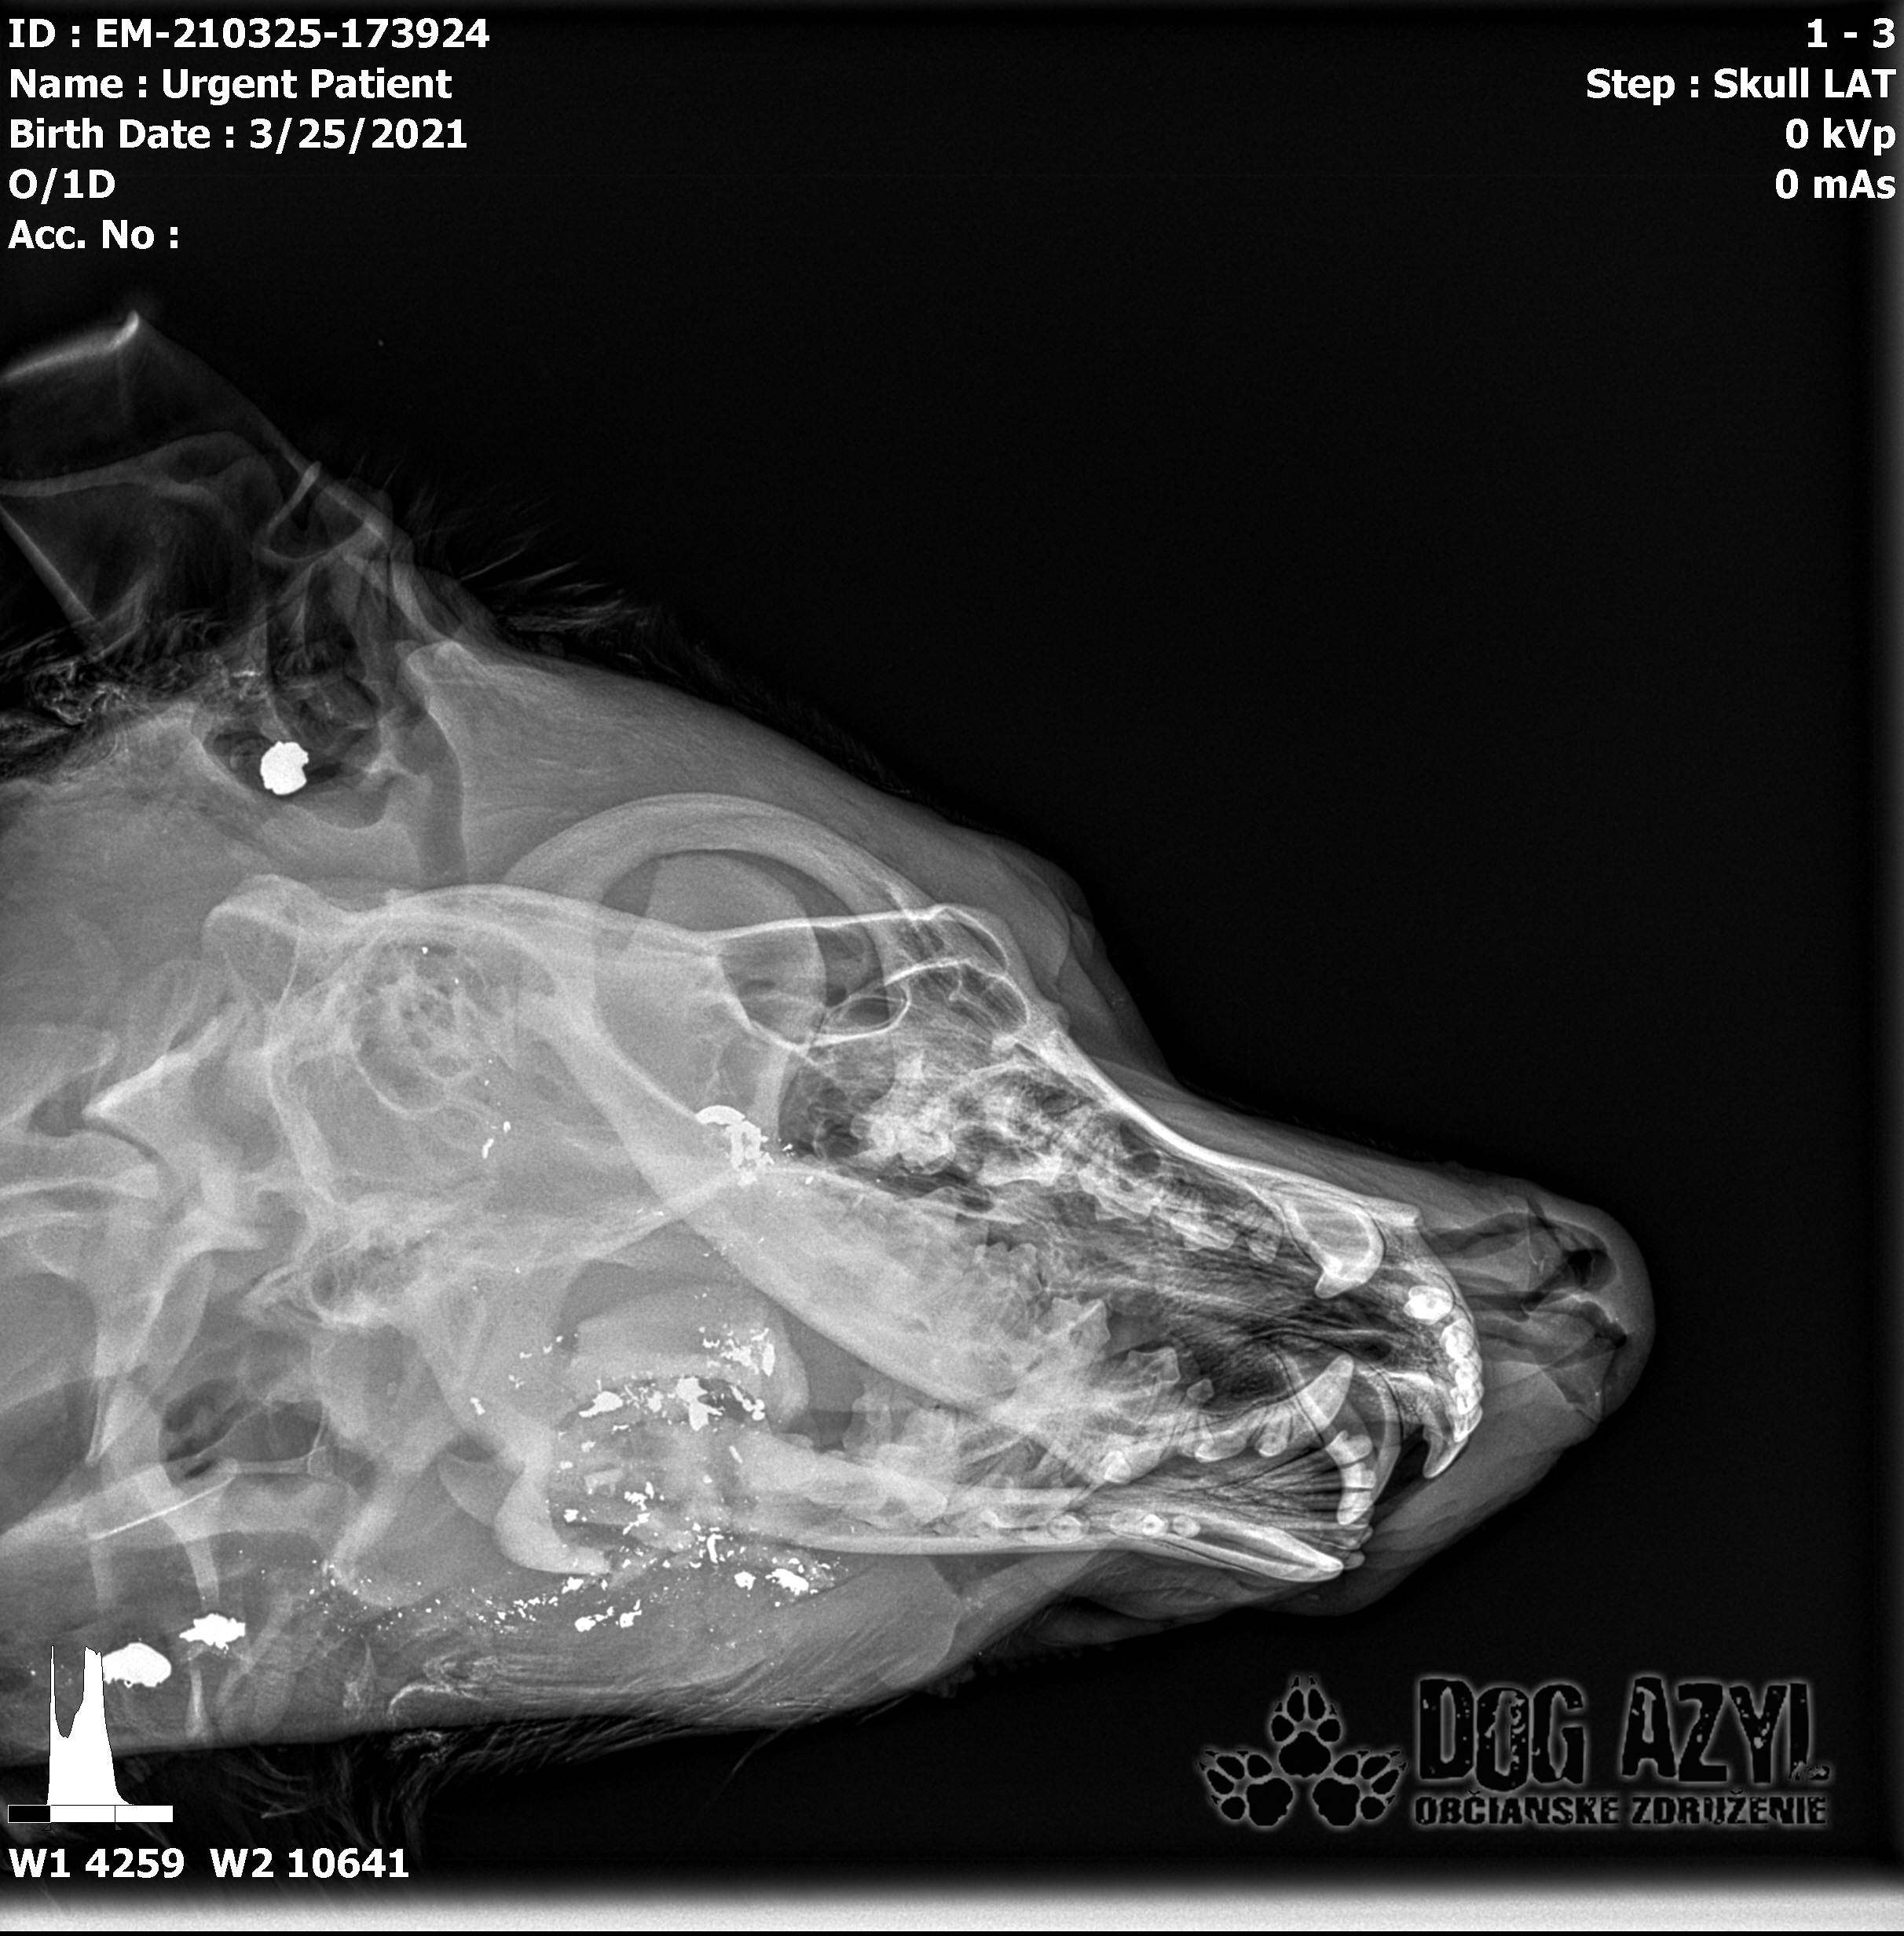

Na druhý deň prišla správa, že Baris má poškodenú krčnú chrbticu a úlomok z náboja mu tlačí na miechu :( Toto bol dôvod jeho čiastočného ochrnutia. Verdikt, okamžitá operácia. Veľmi náročná operácia, ktorá nevedela zaručiť, že Baris bude chodiť. On to ale vedel už vtedy!

Včera bol odovzdaný do rúk najlepších špecialistov na veterinárnu kliniku Sibra centrum. Boli mu urobené všetky vyšetrenia, vrátane MRI a CT. Zistilo sa, že slabosť v jeho ľavej strane a dôvod, prečo sa nevie postaviť, je spôsobená fragmentom medzi 4. a 5. stavcom, ktorý tlačí na miechu. Padol verdikt, okamžitá operácia. Dnes už má za sebou veľmi náročnú, niekoľkohodinovú operáciu, ktorá podľa slov MVDr. Vatolíka dopadla dobre, ale v takomto stave a po takto náročnej operácii sa prognóza nedá určiť.

Strela zasiahla Barisa v oblasti lícnej kosti, ktorá mu rozdrvila sánku a následne putovala cez krk až po krčnú chrbticu. Úlomky z guľky (neviem ako sa to odborne volá) sa roztrieštili na "milión" kusov počas svojej cesty. Tieto úlomky sú všade (ako vidieť aj na RTG). Jeden (alebo niekoľko týchto úlomkov) sa dostali až po miechu, ale našťastie ju neprerazili. Toto spôsobilo, že Baris citlivosť v nohách na ľavej strane sice má, ale má poškodenú motoriku. Tieto úlomky sa z oblasti stavcov, miechy aj krku dnes odstránili, ale Barisko z ďaleka nemá vyhraté. Miecha je totiž zakrvácaná (opäť sa ospravedlňujem za nepresnosť a laickosť) a to, že ako veľmi je poškodená, alebo či jeho slabosť bola spôsobená "iba opuchom" sa ukáže cca do 24 hodín. Ak Baris nedajbože do zajtra stratí citlivosť v nohách, tak.. žiaľ... Ale! ak citlivosť zostane, prípadne nastane aj zlepšenie, tak vzplanie plamienok ďalšej nádeje a bojujeme ďalej!